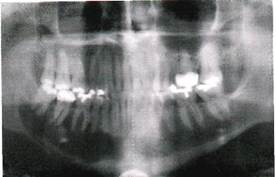

Клиника. Миксома (миксофиброма) растет медленно, безболезненно, проявляется вздутием кости. Пальпаторно определяется плотное, безболезненное выпячивание челюсти с гладкой поверхностью. Слизистая оболочка над опухолью в цвете не изменена. Зубы в границах новообразования подвижные, смещаются. При локализации патологического очага вблизи нижнечелюстного канала возникает симптом Венсана. На верхней челюсти миксома может прорастать в верхнечелюстную пазуху и полость носа.

Рентгенологическая картина. Определяется очаг деструкции костной ткани с нечеткими границами. В некоторых случаях может иметь вид мелких ячеистых образований, разделенных костными перегородками.